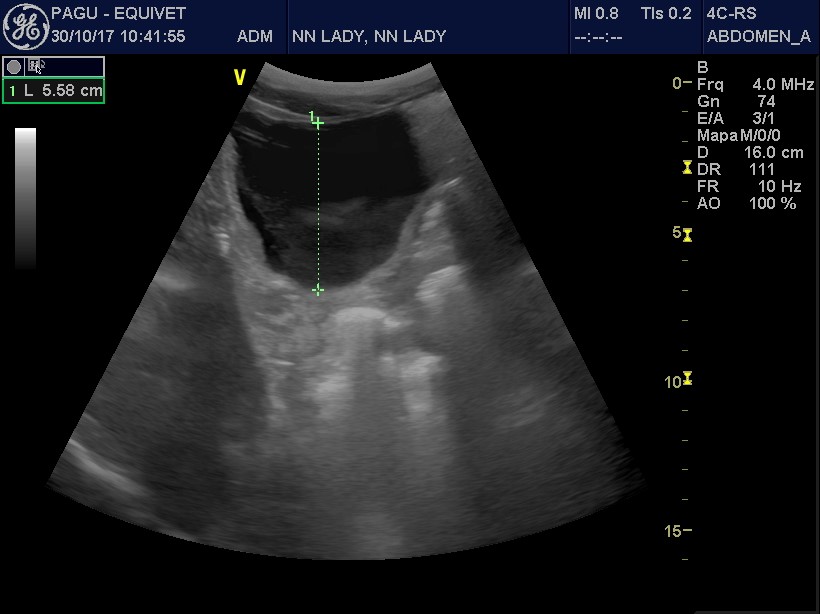

Durante a ultrassonografia transabdominal foram constatadas regiões que sugeriam retenção de mecônio e repleção vesical severa (Imagem 1). Diante disso, prontamente realizou-se sondagem uretral para descompressão recuperando-se 5 litros de urina. Para a retenção de mecônio foram iniciadas terapia laxativa enteral e fluidoterapia parenteral, assim como enema com acetilcisteína. A sonda uretral foi fixada inicialmente, para acompanhamento da eficiência do esvaziamento vesical através da ultrassonografia transabdominal, o que evidenciou repleção vesical persistente. Após constatarmos a ineficiência no esvaziamento, a sonda foi mantida por 4 dias, e aberta a cada 1 hora.

Imagens 2 e 3: Ilustram redução da repleção vesical na imagem ultrassonográfica e eliminação espontânea de urina após 4 dias da admissão.